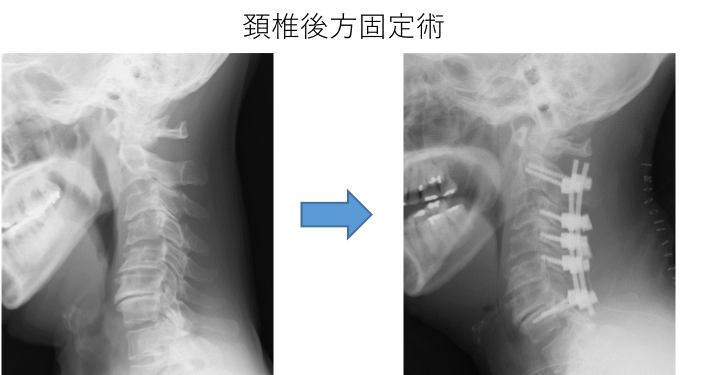

変形性頚椎症・頚椎不安定症・頚椎骨折

骨である頚椎自体の変形やずれ、不安定性がある場合は神経症状だけでなく、首の痛みや動いたときの症状の増悪などの症状をともないます。また、怪我・外傷によって同じことが起こり得ます。

この場合は骨である頚椎自体の治療のため、頚椎固定術が必要となります。椎弓根スクリューや外側塊スクリューを組み合わせた後方固定術を行います。必要があれば頭蓋骨からの連続した固定術も行います。

頸椎後方固定術 頭蓋頸椎後方固定術